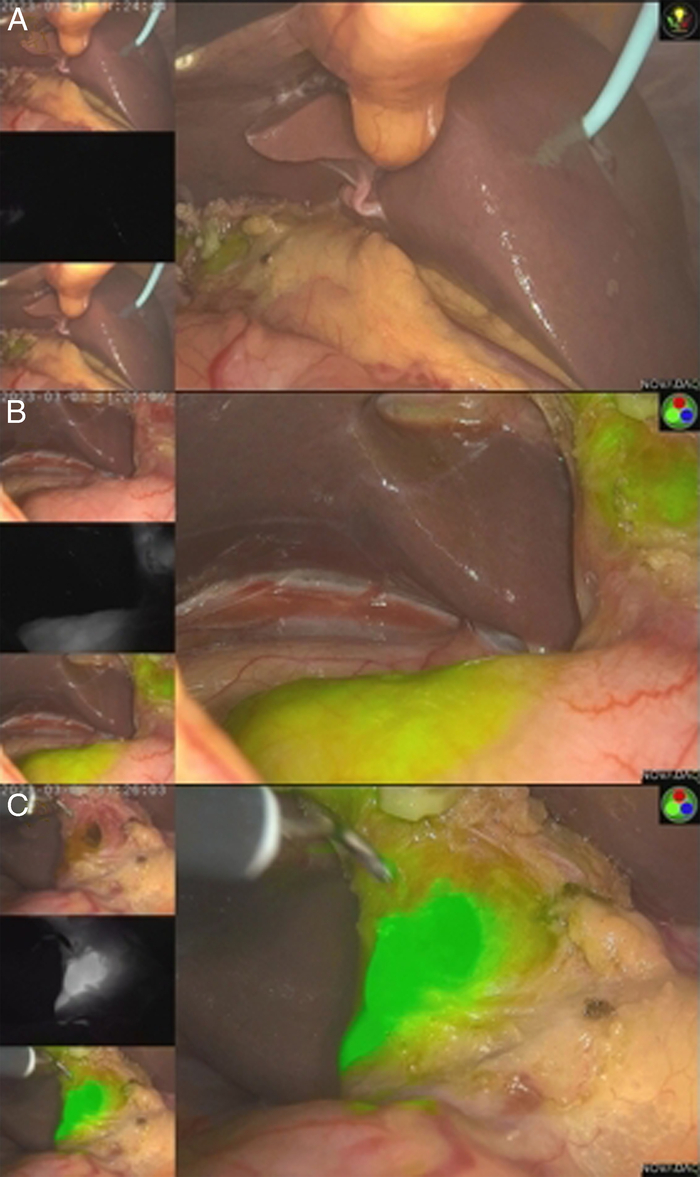

Methods: The clinical data of patients who underwent elective reoperation of the biliary tract in our department between January 2020 and June 2022 were retrospectively analyzed. ICG was injected peripherally before the operation, and near-infrared light was used for 3-dimensional imaging of the bile duct during the operation.

Abstract Image